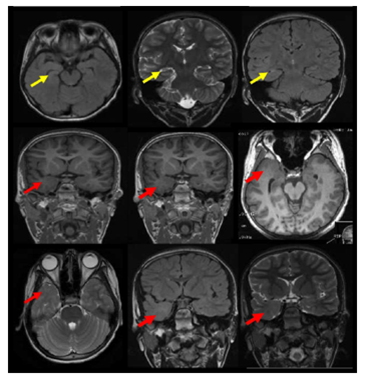

A twelve years old right handed boy a school student referred to the epilepsy monitoring unit for epilepsy surgery evaluation of pharmaco-resistant epilepsy that failed several antiepileptic drugs monotherapy and poly therapy trials. The patient is a product of full term normal spontaneous vaginal delivery with normal mile stones. He had febrile convulsions at the age of one year with no recurrence and had family history of epilepsy with one sibling and one paternal cousin had epilepsy with generalized tonic clonic seizures in remission on anti epileptic drugs. The first generalized tonic clonic seizure occurred at the age of seven years preceded by an aura of rising abdominal pain and followed by post ictal fatigue. Generalized tonic clonic seizures recurred at weekly interval with and without the preceding abdominal pain. At times the abdominal pain occurs with no generalized tonic clonic seizures but followed by lack of concentration and fatigue. The seizures occurred mainly during wakefulness but could occur during sleep. The patient never achieved seizure remission and never developed status epilepticus despite frequent seizures. He was admitted to the epilepsy monitoring unit EMU at the age of twelve years. He was on two antiepileptic drugs namely topiramate one hundred milligram twice daily and lamotrigine two hundred milligram twice daily with almost weekly seizures. His neurological, general and systemic examinations were normal. The patient was kept on his antiepileptic drugs and had five days video electroencephalography EEG monitoring using ten-twenty system scalp EEG electrodes with additional anterior temporal electrodes T1 electrode on the left anterior temporal region and T2 electrode on the right anterior temporal region respectively. During the video EEG monitoring the patient developed four stereotyped electroclinical seizures. Three were during wakefulness and one during sleep. No generalized tonic clonic seizures recorded. The seizures were preceded by abdominal pain in one seizure only. The seizure semiology starts with abrupt asymmetric abduction of both upper and lower limbs with prominent tonic and dystonic contraction of the left upper and lower limbs and adversive eyes and head deviation to the left with proximal automatic movements of the right arm and leg. The duration of seizure was fifty to sixty seconds during which the patient was unresponsive with early recovery of comprehension and speech in the post ictal phase. The ictal EEG onset starts with right frontal regional suppression followed by slow activity of the right hemisphere in all recorded seizures. The interictal EEG showed asymmetric background with excessive slow transients of three to five hertz activity in the right hemisphere with frequent repetitive interictal spikes and polyspike-wave discharges at right frontopolar region intermixed with two to three slow transients (Figure 1). The electroclinical seizures recorded favored right hemispheric epilepsy with early engagement of the right frontal regions. Preadmission MRI of the brain showed right hippocampal sclerosis HS. Ictal single-photon emission computed tomography SPECT with technetium-99m hexamethyl-propylene amine oxime Tc-99m HMPAO injected at twenty five seconds after ictal EEG onset of the fourth seizure showed right medial and lateral temporal lobe hyperpefusion (Figure 2). Interictal positron emission tomography with F-18 fluorodeoxyglucose F-18 FDG-PET showed right hemisphere hypometabolism with marked reduction of F-18-FDG metabolism at right frontal, right temporal, right parietal and right thalamic regions (Figure 3). As the initial MRI diagnosis of right HS could not alone explain the seizures of the patient with a high probability of additional right hemispheric neocortical focus a follow up high resolution three Tesla MRI brain was performed prior to invasive EEG recording. The MRI brain clearly demonstrated right temporal pole cortical dysplasia in addition to the right HS (Figure 4).The diagnosis of dual pathology was made with right temporal pole cortical dysplasia and right HS the so called HS+. The patient underwent directly epilepsy surgery without invasive EEG implantation .He received extensive right temporal lobectomy under intraoperative electrocorticography and regions with active spiking were removed (Figure 5). Histopathology of the resected right hippocampus showed HS and tissue from the right temporal pole confirmed the presence of focal cortical dysplasia type III. The patient had no post surgical complications. The patient became seizure free and six month post epilepsy surgery interictal EEG was normal. Currently the patient is seizure free with significant cognitive improvement at five years post epilepsy surgery on lamotrigine 25mg once daily .He attends high school and plans to be a teacher.

Figure 4 The MRI brain demonstrates right temporal dual pathology. Right HS with atrophic changes of the right hippocampus with architecture distortion and increased signal intensity on coronal T2 and FLAIR and axial FLAIR weighted images is demonstrated ( yellow arrows).In addition right temporal pole cortical dysplasia is shown with smaller right temporal pole ,blurred grey white junction in the right temporal pole on axial and coronal three-dimensional spoiled gradient recalled acquisition in steady state 3-DSPGR images and smaller right temporal pole with blurred grey white matter junction and increased signals on axial T2 and coronal T2 and FLAIR weighted images (red arrows).